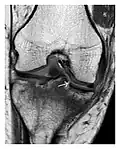

Occult osseous injuries may result from a direct blow to the bone by compressive forces of adjacent bones against one another or by traction forces during an avulsion injury. Lesions in the tibial plateau, hip, ankle, and wrist are often missed. In a tibial plateau fracture, any disruption of the posterior and anterior cortical rims of the plateau should be sought. Impaction of subchondral bone will appear as an increased sclerosis of the subchondral bone (Figure 1). In the hip, posterior acetabular fractures also present subtle radiographic findings. The acetabular lines should then be carefully examined keeping in mind that the posterior rim, which is harder to see on X-rays, is more frequently fractured than the anterior rim (Figure 2). In the wrist, detection of carpal bone fractures is often challenging, with up to 18% of scaphoid fractures radiographically occult. Carpal fractures, especially the scaphoid, are associated with the risk of avascular necrosis. In apparently normal wrist radiographs from symptomatic patients, if there is history of a fall on an outstretched hand with pain in the anatomic snuffbox, suggesting scaphoid injury, the initial examination with posteroanterior, lateral, and pronation oblique views must be complemented by other specific views such as supination oblique and the "scaphoid" view A careful examination of cortices for evidence of discontinuity or offset and cancellous bone for lucency is necessary (Figure 3).[1]

Figure 1: A 56-year-old woman presenting with left knee pain after a fall. (a) Initial anteroposterior radiograph was considered normal, however, subtle cortical disruption of the anterior rim of the medial tibial plateau, medial to the tibial spine, is noted (arrow). (b) Coronal T1-weighted MRI confirms the cortical disruption (arrow) and shows extensive fracture through the proximal tibia. (c) Coronal proton density-weighted image with fat saturation shows extensive edema in the subchondral bone. Note also hypersignal adjacent to the medial collateral ligament corresponding to a grade I sprain (arrowheads).[1]